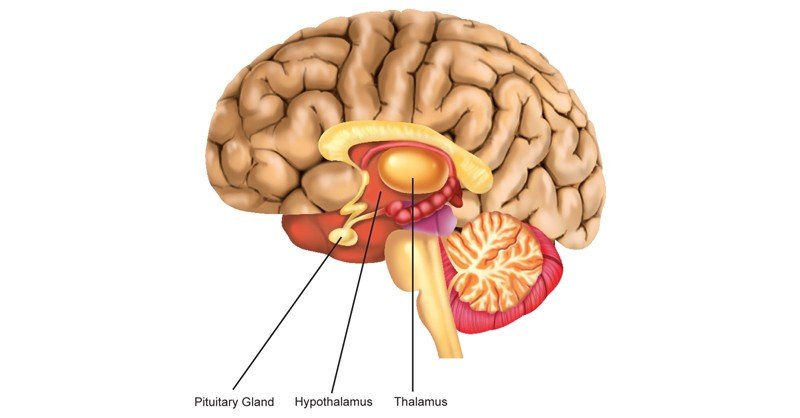

Как работает центр насыщения в гипоталамусе: визуальные иллюстрации